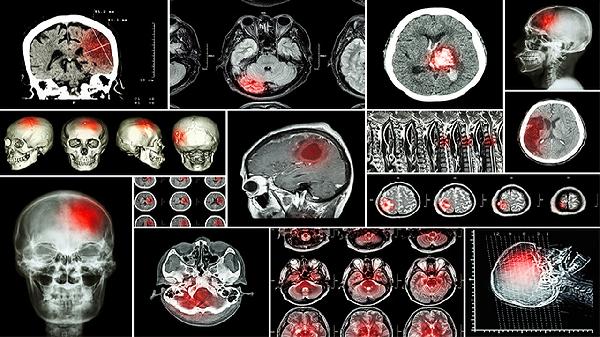

少数情况下,侧脑室增宽可能伴随染色体异常或颅内结构畸形。如合并透明隔腔消失、小脑发育异常等征象时,需考虑18三体综合征、神经管闭合不全等疾病可能。此时建议进行胎儿磁共振检查评估脑实质发育情况,同时通过羊水穿刺或无创DNA检测排除染色体异常。若确诊为病理性脑室增宽,需由产科与儿科医生共同制定后续监测方案。